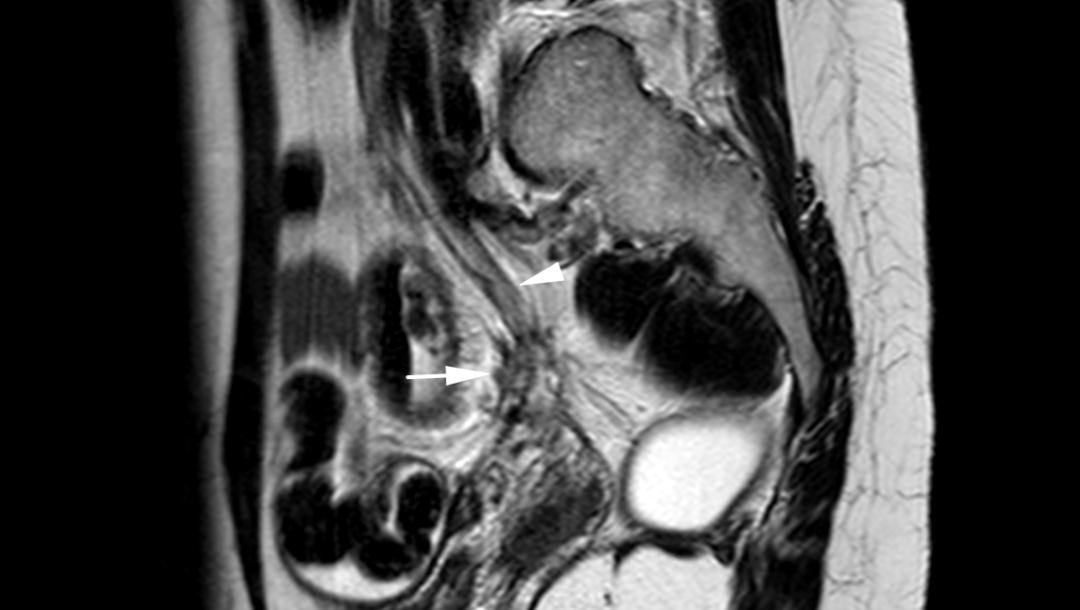

子宫内膜异位至右侧卵巢,T2WI 矢状位呈类圆形高信号,注意的是同时异位至道格拉斯窝及宫颈后区,T2WI 矢状位显示病灶呈低信号,中间夹杂更高信号结节,T1WI 轴位显示病灶多发高信号结节(提示多发出血点)

子宫内膜异位至左侧子宫骶韧带,T2WI 轴位子宫骶韧带前方结节样低信号,边缘不规则呈星芒状